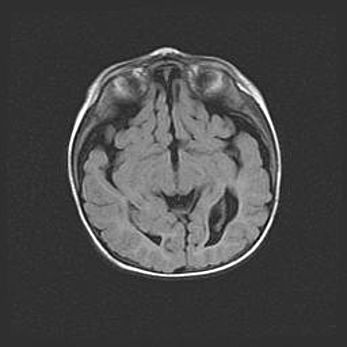

Открытая гидроцефалия.

Возраст: 9 месяцев 12 дней

Вес: 6800 г

Пол: мужской

Окружность головы: 41,5 см

Срок гестации: 28 недель

Гидроцефалия головного мозга у новорожденных имеет характерный признак: опережающий рост окружности головы приводит к визуально хорошо определяемой гидроцефальной форме сильно увеличенного в объёме черепа. Детские неврологи определяют следующие симптомы гидроцефалии у грудничков: выбухающий напряжённый родничок, частое запрокидывание головы, смещение глазных яблок к низу.